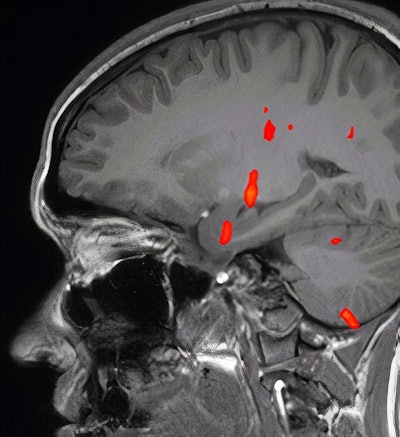

Although the patient was treated conservatively and started to recover, she then began to suffer from sensations of offensive odor (cacosmia) and taste (cacogeusia). Functional MRI was useful in evaluating the patient, whereas clinical exams had appeared to be normal; CT of the paranasal sinuses had been unremarkable; and no abnormalities in the olfactory bulbs and sulci were seen on brain MRI studies, the authors reported.

Blood oxygenation level-dependent (BOLD) activation on fMRI studies has been associated with olfactory sensation, a complex activity in the brain that involves the amygdala, the orbitofrontal cortex, and other structures, Gad and Ismail wrote.

The patient in the case report experienced taste and smell dysfunction for three months and had been referred to a neurology clinic, where she had a normal examination. Clinicians performed a task-based functional MRI study that involved exposure to smells and the generation of BOLD activation maps. Activation was not seen in the orbitofrontal cortex, while there was a strong BOLD signal in the right uncus/piriform cortex, they reported.